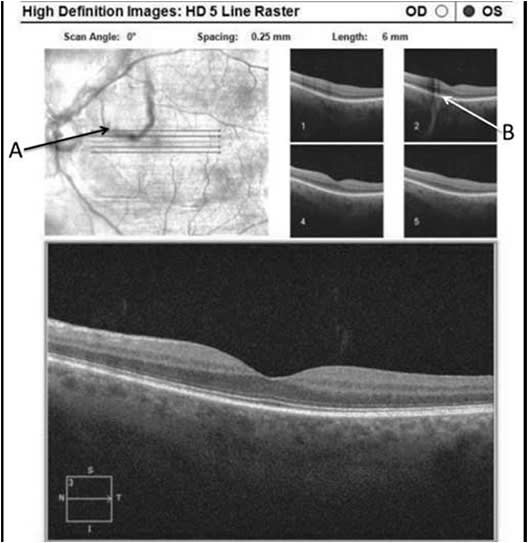

Qualitative analysis of the effects of LFT have been achieved with spectral domain OCT (SD-OCT) and scanning laser ophthalmoscopy by comparing shadows on the retina created by floaters before and after treatment. A recent study published in OSLI Retina in October 2018 on novel OCT applications, including shadow changes on a 5-line raster scan following vitreolysis, described cases in which patients had complained of a scotoma that would not go away.6 Multiple initial tests from other doctors did not reveal an etiology.

After further examination of the vitreous and evidence on SD-OCT of the shadow being cast by a large floater over the macula, YAG vitreolysis was performed. Following treatment, patients described resolution of the floater and the SD-OCT scans revealed resolution of the shadow that was cast on the retina (Figures 11 and 12).